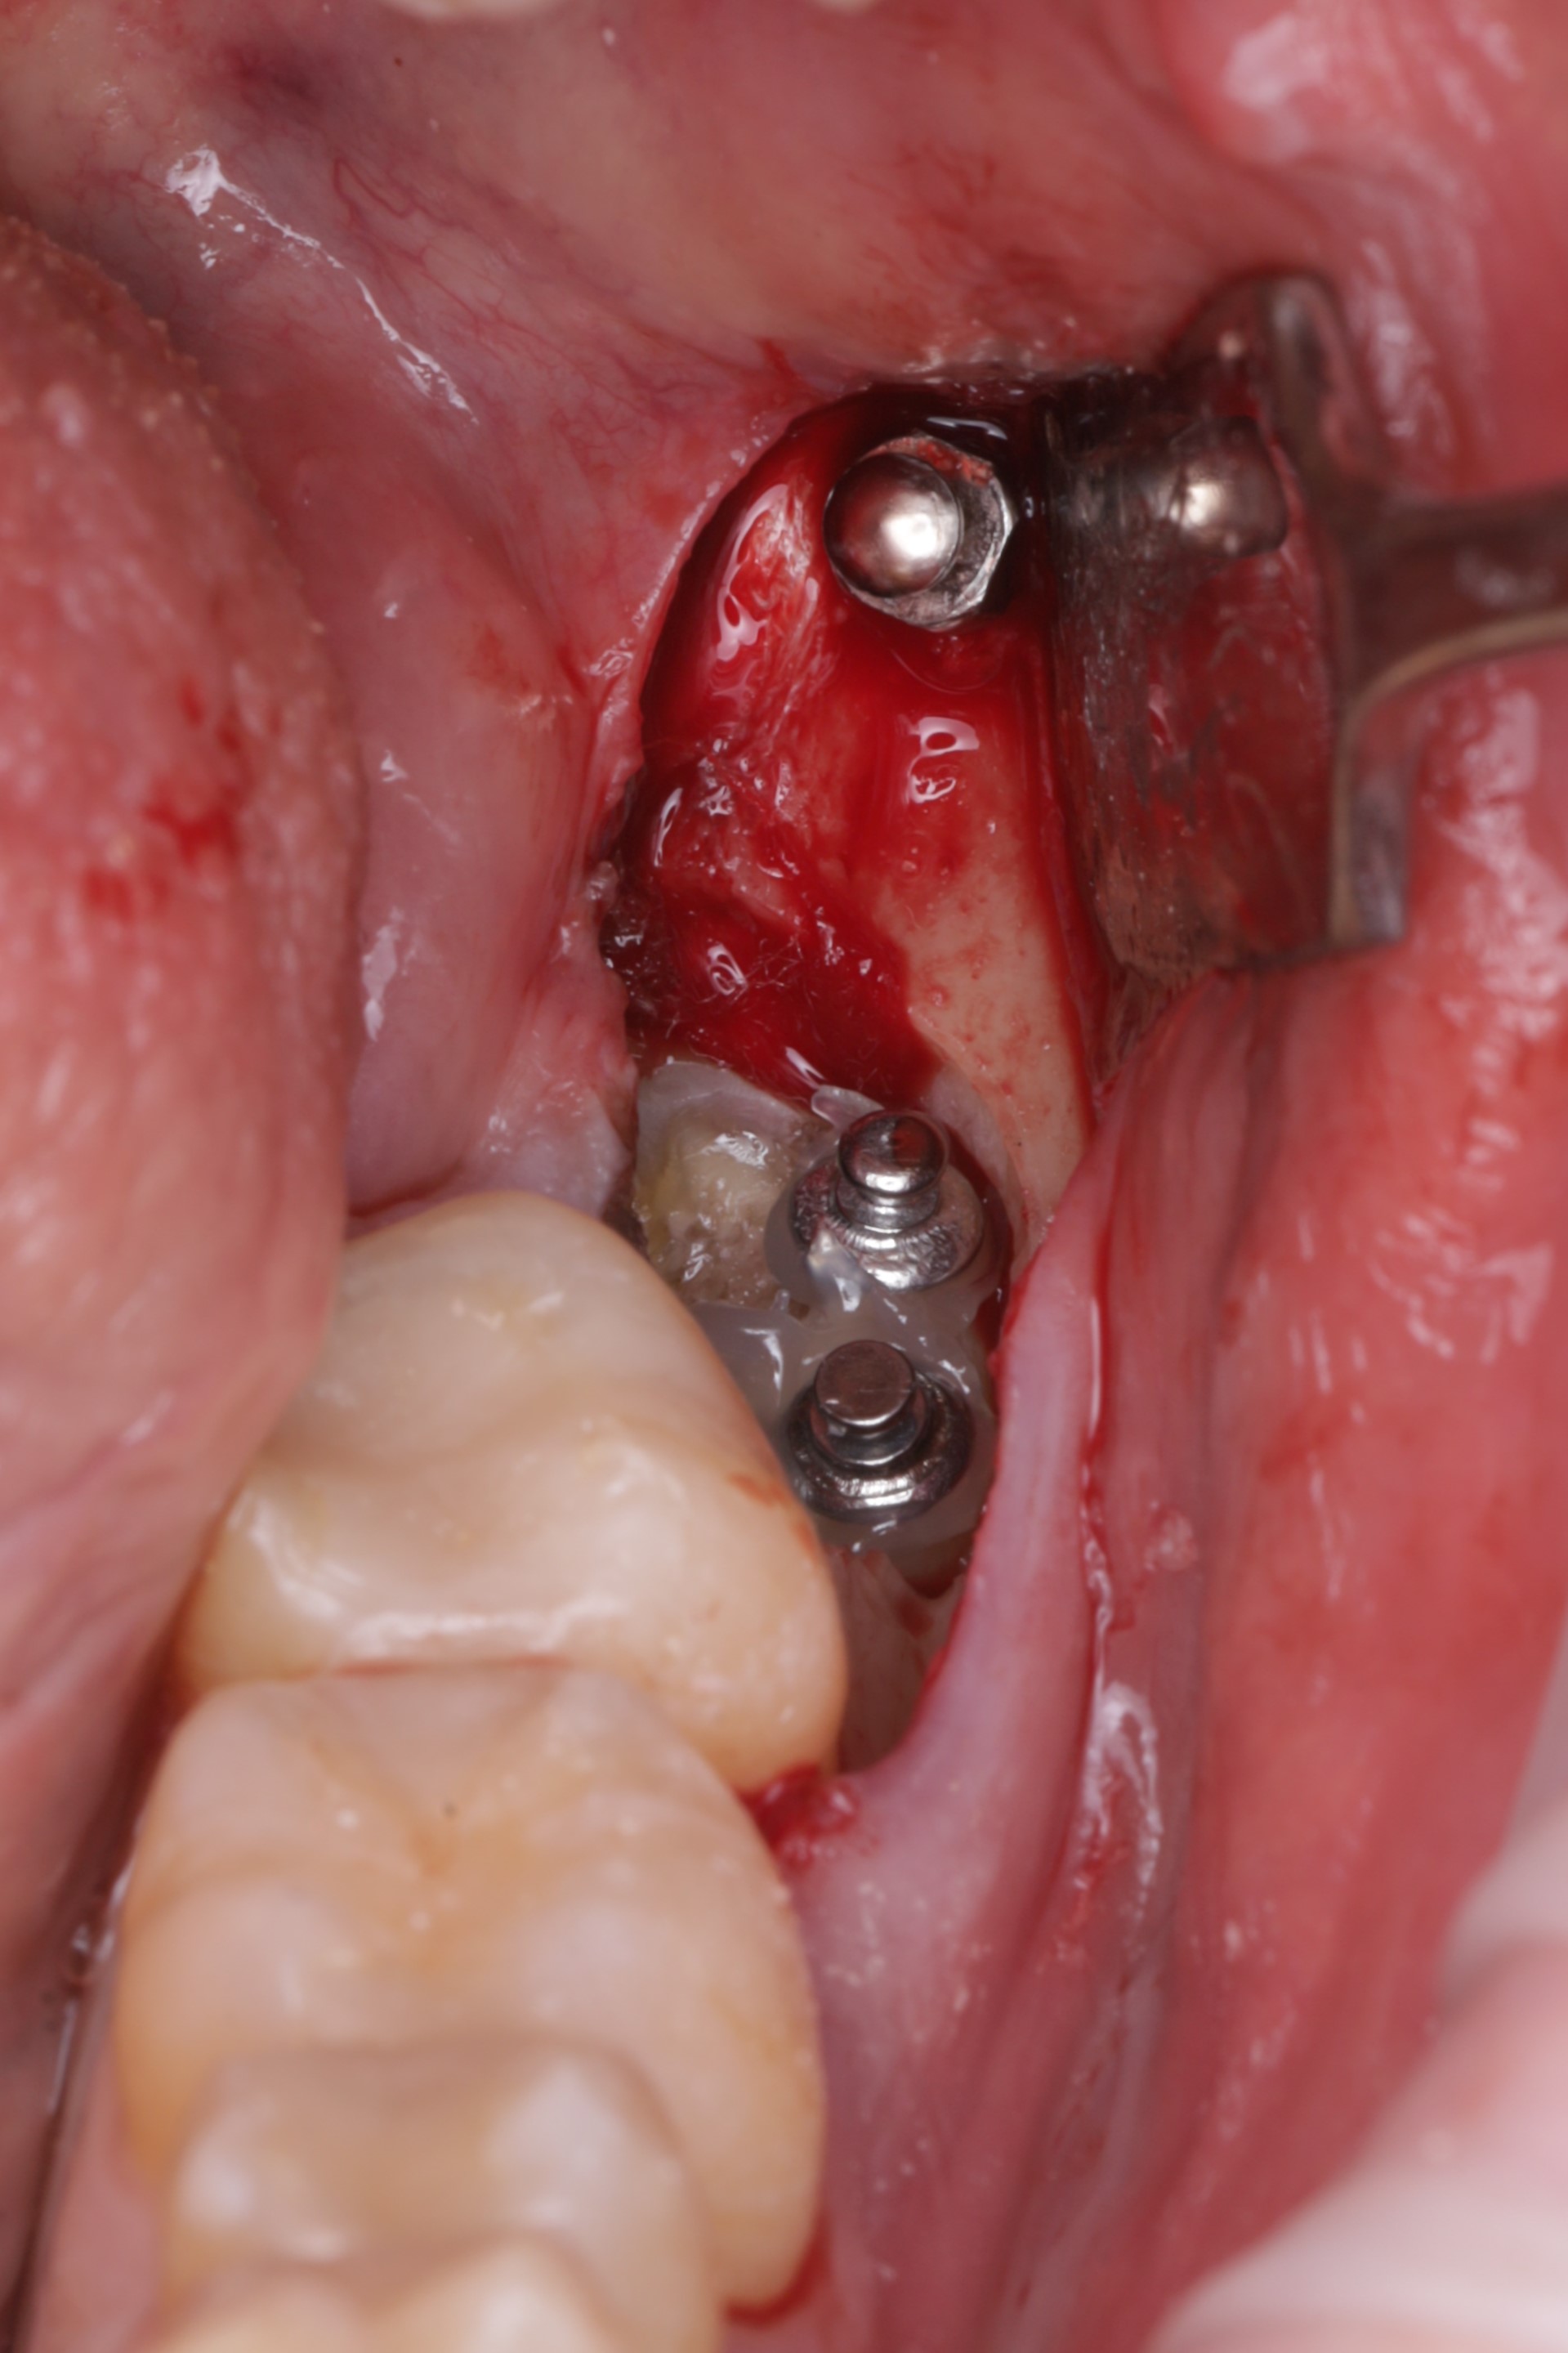

Установлен ортодонтический минивинт и три кнопки

Произвдена активация с помощью ортодонтичечских тяг